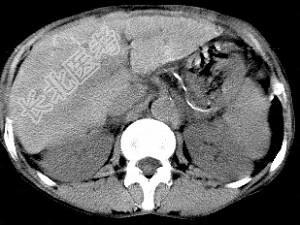

- 单项选择题男,40岁有血吸虫感染史, 腹胀不适,食欲减退, CT扫描所见如图,最可能的诊断是 ( )

A、肝炎后肝硬化

B、血吸虫后肝硬化

C、酒精性肝硬化

D、胆汁性肝硬化

E、脂肪肝